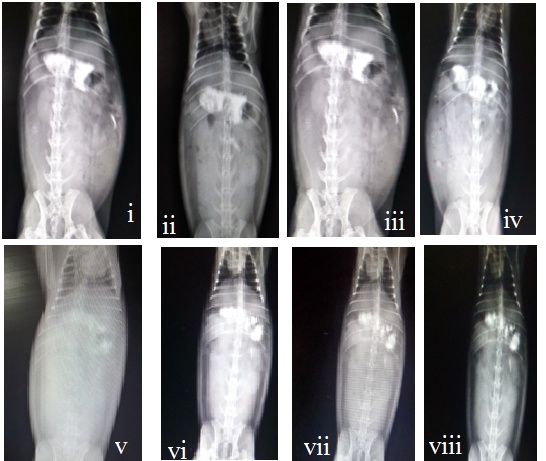

Fig. 4: In vivo X-ray images showing the presence of optimized formulation in the stomach region of the rabbit at i) 0h ii) 1h iii) 2h iv) 4h, v) 6h, vi) 8h, vii) 10h viii) 12 h

In vivo x-ray imaging studies

The X-ray imaging study was performed on the rabbit to check the floating behavior of the optimized formulation. The X-ray images were taken immediately after administration, after 1 h 2 h, 4 h, 6 h, 8 h, 10 h and 12 h of gel administration. It was found that oral floating in situ gel was floated immediately after administring to the rabbit and it was observed to be floating in the stomach for 12h. Results of the X-ray imaging study are given in fig. 6.

X-ray imaging studies for floating of the formulation [16, 21]

A The study was employed using 2.5 kg healthy rabbit which was housed for 72 h, had free access to water and food and fasted for 12h prior to the study, but the water was allowed. The optimized lornoxicam in-situ gel formulation prepared by loading 15%w/v BaSO4 as a radio-opaque agent in place of the drug was administered orally using the animal oral feeding tube. Throughout the experiment, the animals fasted with free access to water, and X-ray images of the rabbit abdomen were taken at pre-programmed time intervals of 0, 1, 2, 4, 6, 8, and 12 h [16, 20, 21].